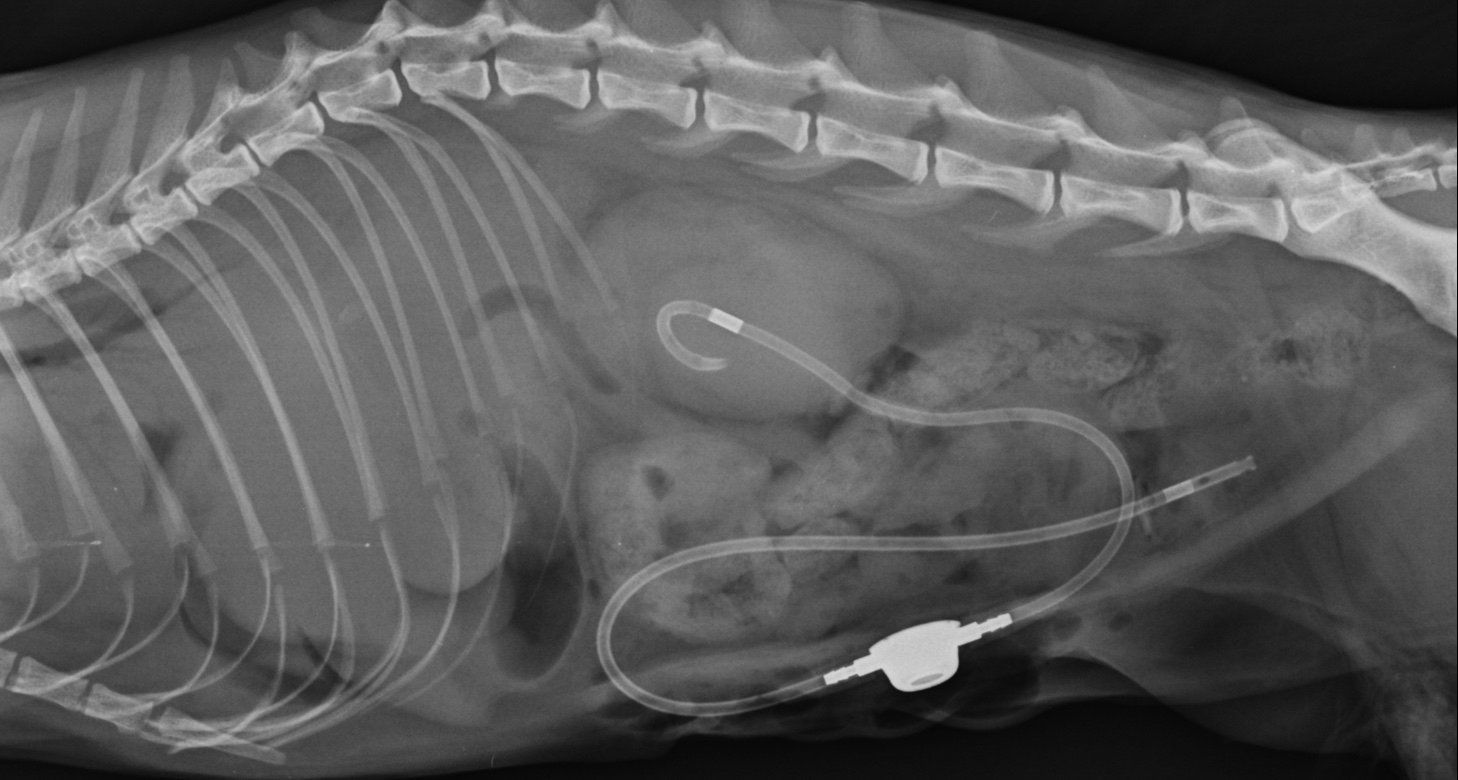

El paladar hendido o fisura palatina es una malformación congénita frecuente en perros de raza. Es un defecto en el cierre del paladar duro y blando, dando como consecuencia una comunicación entre la cavidad oral y nasal. Los síntomas más frecuentes son los ronquidos, neumonía por aspiración, dificultad en la ingesta y estornudos. El tratamiento siempre es quirúrgico. Es necesaria una cirugía para reconstruir el paladar y cerrar la comunicación entre ambas cavidades. Para que el paciente tolere mejor la cirugía y la anestesia, es recomendable operar a partir de los 2 meses de edad. Si fuera necesario se podría colocar una sonda nasogástrica para garantizar su alimentación y poder posponer la cirugía el tiempo necesario para que sea adecuado someterle a cirugía. La técnica más frecuente para esta patología es realizar un flap de 180º del paladar duro. Se puede utilizar tanto sutura monofilamento como multifilamento para evitar que los puntos molesten en la cavidad oral al paciente. Se realizan puntos en U para liberar tensión. Como en toda cirugía reconstructiva es muy importante respetar la vascularización del tejido, y dejar la mínima tensión en los tejidos. A continuación les mostramos imágenes de la cirugía: